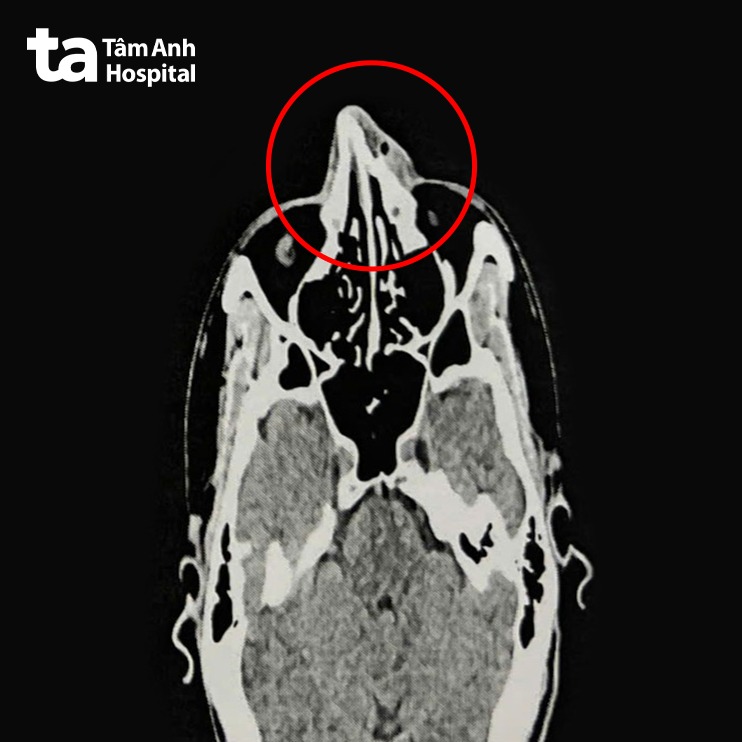

ThS.BS.CKI Nguyễn Trung Nguyên, Trung tâm Tai Mũi Họng, Bệnh viện Đa khoa Tâm Anh TP HCM, cho biết kết quả nội soi và chụp CT 128 lát cắt ghi nhận xương mũi của anh Phi bị gãy ở vị trí tháp mũi, phù nề tụ khí mô mềm vùng mũi, lệch vách ngăn mũi, viêm mũi xuất tiết. Anh Phi được chỉ định phẫu thuật nâng xương mũi, chỉnh hình vách ngăn mũi.

Anh Phi được điều trị nội khoa ba ngày để giảm phù nề, mũi hết sưng viêm trước khi nhập viện phẫu thuật. Người bệnh được gây mê toàn thân. Qua nội soi kết hợp CT, bác sĩ Nguyên thấy mũi biến dạng, gãy di lệch tháp mũi và ngành lên xương hàm hai bên. Bác sĩ tiến hành chỉnh hình vách ngăn mũi, rạch niêm mạc vách ngăn phải bị vẹo, tách phần sụn tứ giác và phần xương vách ngăn bị vẹo, cắt bỏ phần xương, sụn vẹo. Sau đó nâng xương chính mũi và ngành lên xương hàm hai bên, chỉnh xương mũi thẳng, cân đối. Cuối cùng, bác sĩ Nguyên đặt gạc meche chặt vào hốc mũi qua cửa mũi trước, cố định xương mũi đã nâng.